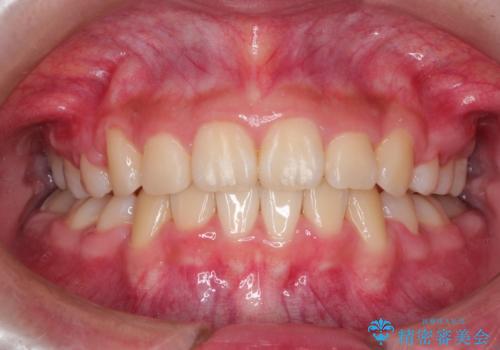

- 上下左右4本の小臼歯を抜歯、ラビアル・ワイヤー矯正を計画した。

抜歯をして第1小臼歯分のスペースを獲得することにより、ガタつきの改善と前歯のリトラクトをおこない、横顔の印象もすっきりとし、整ったEラインを作ることができました。